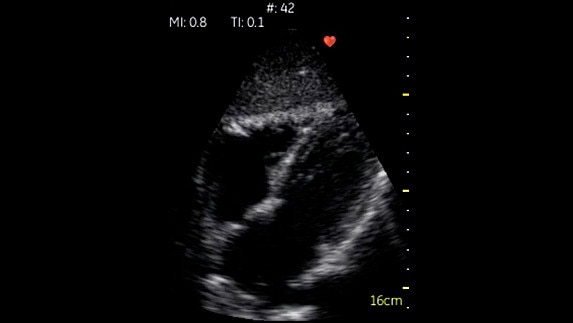

Fazlı Kardiyak